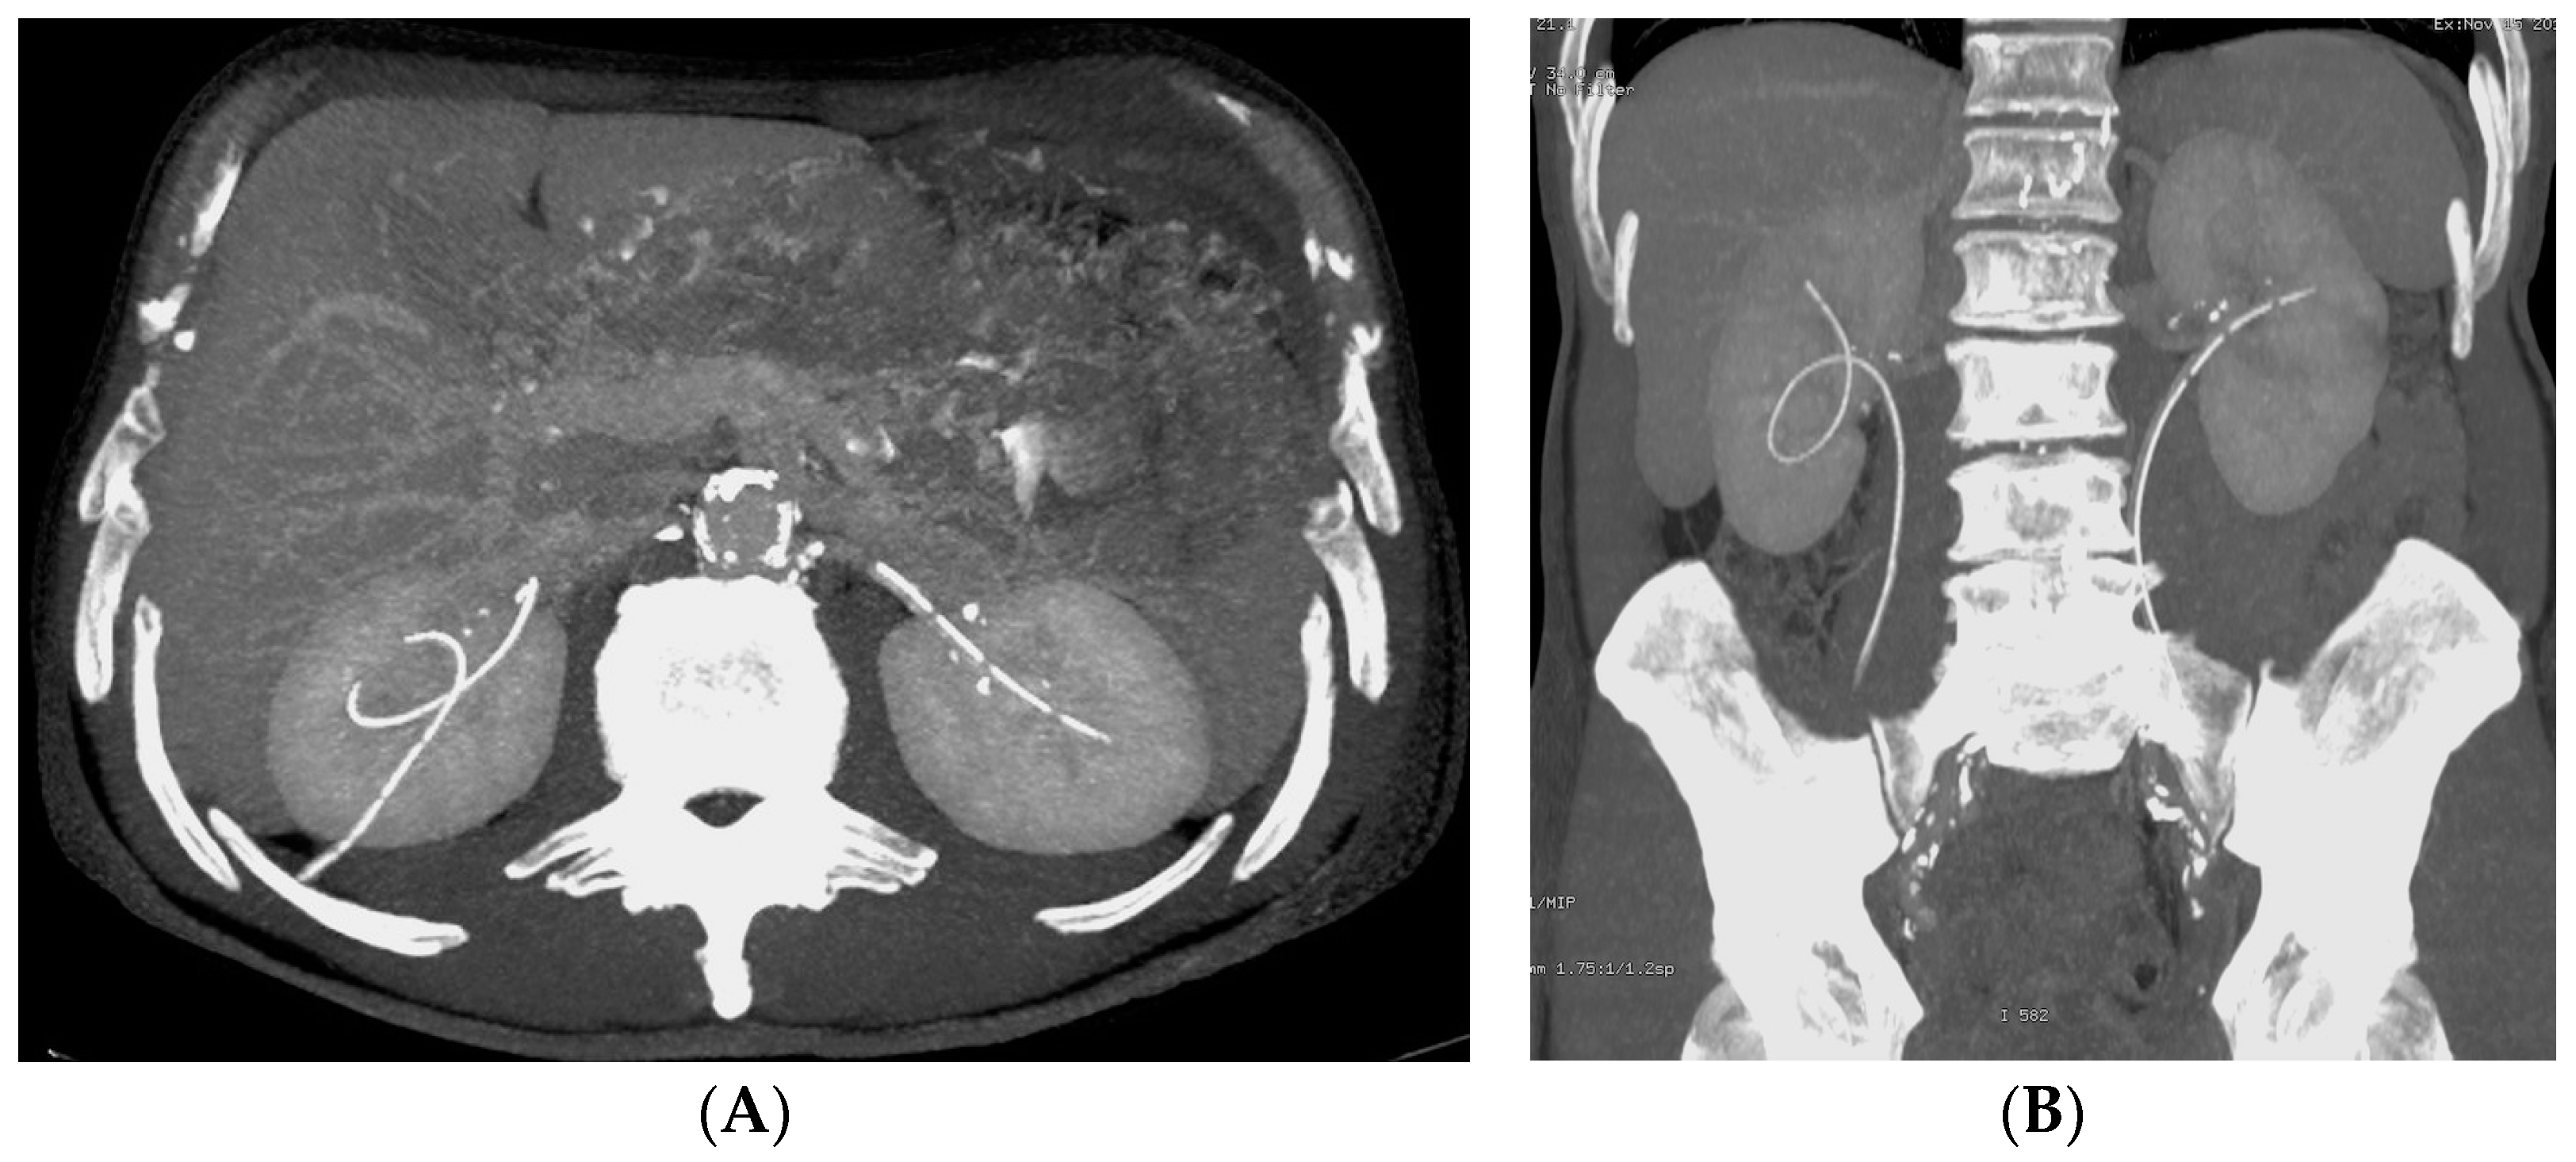

- Malposition: The malposition of a stent is defined as an incorrect position relative to initial placement, while displacement presents a subsequent occurrence in a device that was previously located in the correct position. A stent improperly positioned might assume a sub-pyelic position when the proximal end fails to reach the renal pelvis and a supravesical position when the distal end is detected within the ureter. The origins of this complication predominantly stem from the placement technique, whether it be endoscopy- or fluoroscopy-guided insertion. This underscores the need to verify the accurate positioning of the stent post-placement. Ensuring an adequate length is essential to reduce the occurrence of this complication (Figure 2, Figure 3, Figure 4, Figure 5 and Figure 6) [21,22].